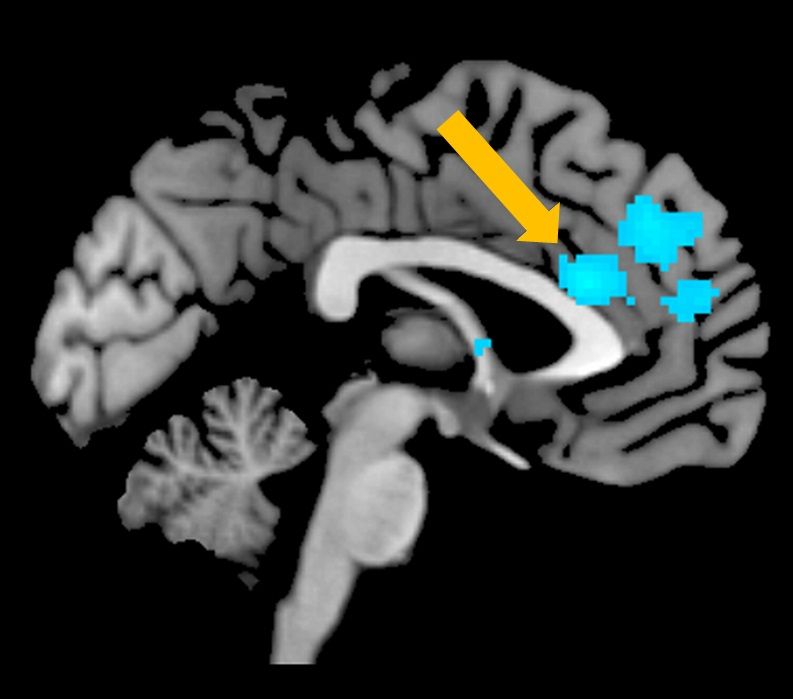

脳活動を調べてみると、サイコパス傾向が高い人は、前部帯状回と呼ばれる、認知的な葛藤の処理に関わるとされる部分の活動が低いということもわかってきた(筆者提供)。